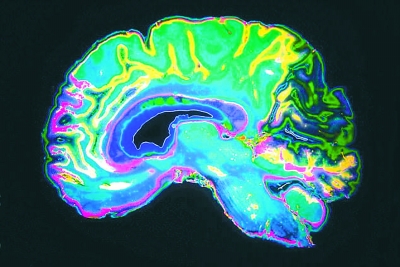

功能性磁共振成像通过探测大脑特殊区域血流变化,从而绘制出大脑活动图。为了进一步完善人工智能算法,研究人员下载了近900名“人类连接体项目”参与者的脑部扫描和智力评分数据。据了解,“人类连接体项目”是美国国立卫生研究院的一个重要项目,目的是增强对人类大脑神经连接的理解认知。